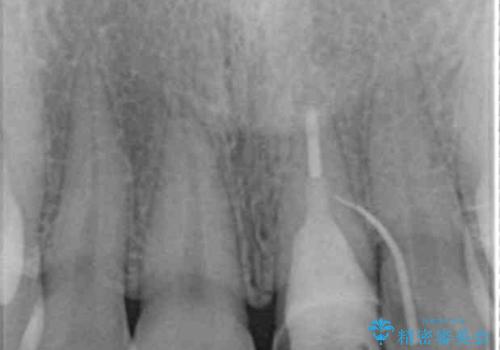

X線検査を行い診断的な小手術を行ったところ、歯に亀裂があり修復が不可能な状態であることがわかりました。

長期的な予後を見通すことが難しかったので、亀裂のある前歯の抜去を行いブリッジで審美性・機能性の回復を行いました。

- 36.3万円(仮歯・ジルコニアクラウン×3)費用は治療当時の料金となります